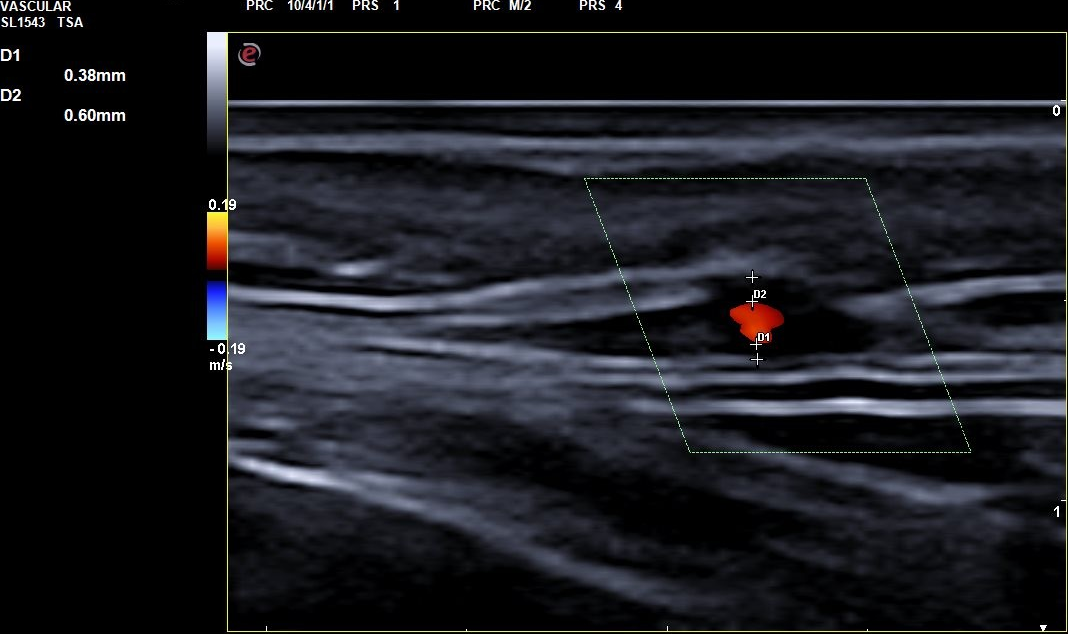

Descripción de los hallazgos ecográficos y las imágenes más relevantes para la resolución del caso

Signo del halo de manera parcheada. Se completa con realización de Doppler de las arterias temporales en ambos lados, observándose en porciones distales en el vaso una hipodensidad sin relleno y disminución del flujo compatible con inflamación del vaso. En tramos proximales se observa buen relleno vascular y flujo sin alteraciones. Todos estos hallazgos con compatibles con alta sospecha de arteritis de la temporal principalmente en sus tramos distales.